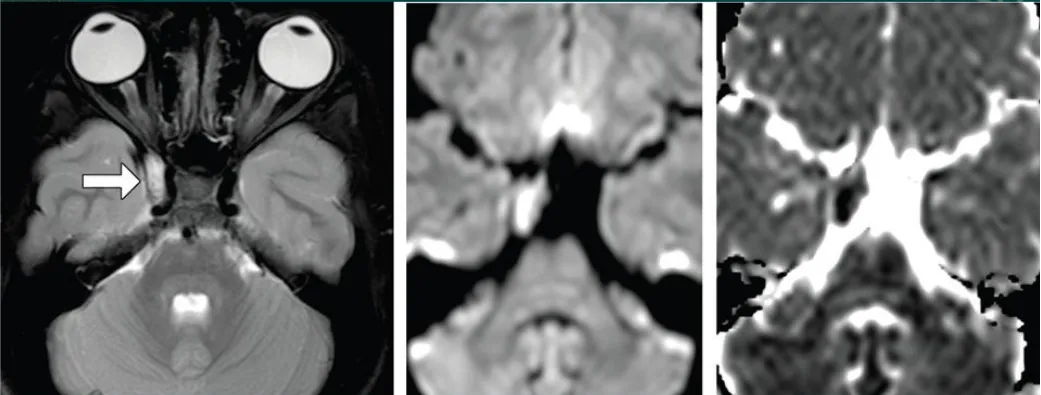

4、皮樣囊腫多為幕下病變,很少發(fā)生在幕上,其首發(fā)部位是鞍上區(qū),很少位于海綿竇區(qū)。海綿竇區(qū)皮樣囊腫又該如何手術(shù),在此結(jié)合一則5歲男孩成功切除海綿竇皮樣囊腫案例說明。原本健康的5歲男孩,有1年的雙側(cè)額葉頭痛、慢性疲勞、復視、上瞼下垂和右眼腫脹。右第三顱神經(jīng)麻痹,伴有右眼球突出、交叉性復視、上瞼下垂、斜視伴右瞳孔散大、瞳孔反射缺失。腦MR顯示在右側(cè)海綿竇側(cè)壁內(nèi)有一邊界清晰的橢圓形病灶,輪廓光滑(圖1)。病人術(shù)后恢復順利,術(shù)后1天進行的CT掃描排除了手術(shù)并發(fā)癥?;颊咝g(shù)后4天出院,無新的神經(jīng)系統(tǒng)癥狀。手術(shù)標本的組織病理學檢查證實腫瘤為皮樣囊腫。術(shù)后2月隨訪中,第三顱神經(jīng)損傷部分恢復:患兒不再主訴復視;眼球突出和上瞼下垂消失;右瞳孔瞳孔反射微弱,眼球內(nèi)收受限緩解。術(shù)后6月MRI研究(圖2)證實完全切除。術(shù)后12個月隨訪中,孩子的眼球運動幾乎完全恢復,右側(cè)瞳孔散大已經(jīng)消失。

圖1:病灶在t1加權(quán)像上呈低信號,周圍有高信號,在t2加權(quán)像上呈高信號且不均勻。增強檢查除了病灶邊邊緣輕微強化,未見增強。病變壓迫海綿竇內(nèi)頸動脈(ICA)。

圖2:海綿竇神經(jīng)血管結(jié)構(gòu)減壓,無腫瘤殘留或復發(fā);術(shù)后FLAIR圖像中術(shù)前高信號完全消失。